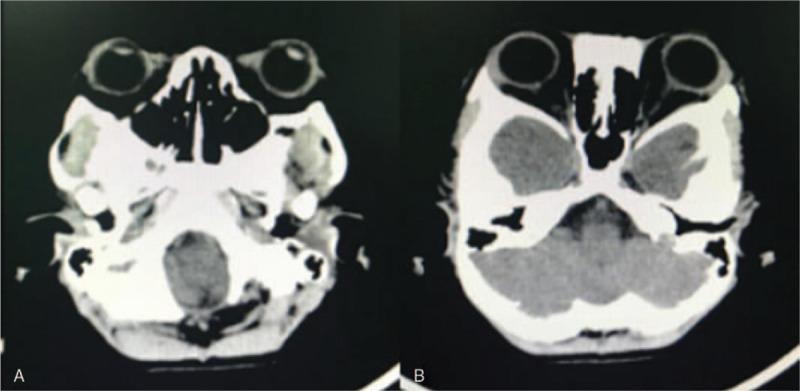

The patient was diagnosed with Crouzon syndrome, and the complications included left proptosis and severe chemosis, confirmed by the clinical manifestations, physical examination, and computed tomography (CT).

患儿被诊断为 Crouzon 综合征,临床表现、体格检查和 CT 检查均提示存在左侧眼球突出和严重球结膜水肿等并发症。

Crouzon syndrome is a craniofacial malformation caused by premature fusion of fibrous sutures in infants. It is one of the most common craniosynostosis syndromes, and surgery is the only effective treatment for correcting it. Postoperative complications such as encephalocele, infections, hematoma have been reported. We herein report a case of a 62-month-old boy with Crouzon syndrome who underwent fronto-orbital advancing osteotomy, cranial vault remolding, and extensive osteotomy and subsequently developed left proptosis and severe chemosis, these complications are rare and we believe it will be of use to clinicians, physicians, and researchers alike.

颅缝早闭症(Crouzon 综合征)是一种颅面部畸形,由婴儿期纤维性缝合过早融合引起。它是最常见的颅缝早闭综合征之一,手术是唯一有效的矫正方法。据报道,术后会出现脑膨出、感染、血肿等并发症。我们在此报告一例 62 个月大的 Crouzon 综合征患儿,行额眶前移截骨术、颅穹窿重塑术和广泛截骨术,术后出现左侧眼球突出和严重球结膜水肿,这些并发症较为罕见,我们认为这对临床医生、内科医生和研究人员都有帮助。